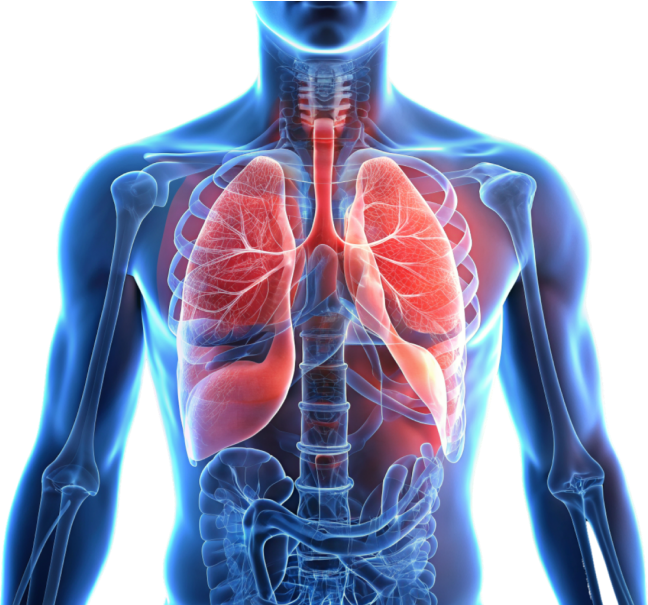

Are you constantly dealing with congestion and mucus buildup? Do respiratory issues disrupt your daily life?

These problems can greatly impact your health and overall well-being. The good news is, there's a natural way to alleviate these symptoms and enhance your health.

Imagine breathing easily, free from congestion, and feeling revitalized every day. This isn't just a dream—it's achievable with the right support.

1. Clear Respiratory Passages

Breathing easily is essential for a healthy, active life. Mucus buildup can hinder your respiratory function, making you feel congested and uncomfortable.

By incorporating natural supplements like Banafsha Extract into your routine, you can effectively clear your respiratory passages.

Banafsha works as a natural expectorant, helping to break down and expel mucus, allowing you to breathe more freely.

Imagine waking up each morning with clear sinuses and an unobstructed airway, ready to take on the day.

2. Boost Immune Health

A strong immune system is vital for maintaining good health and preventing illnesses.

Banafsha is renowned for its immune-boosting properties, helping to strengthen your body's natural defenses.

By purifying the blood and removing toxins, Banafsha supports your immune system, making it easier to fend off infections and recover more quickly when you do get sick.

4. Reduce Inflammation

Chronic inflammation can lead to various health issues, including respiratory problems and skin conditions.

Banafsha has powerful anti-inflammatory properties that help reduce inflammation throughout the body.

This can alleviate symptoms of respiratory issues and improve skin health, giving you a clearer, more radiant complexion.

5. Enhance Mental Clarity

Mental clarity is essential for productivity and success. However, congestion and respiratory issues can often cloud your mind, making it difficult to focus.

Banafsha supports cognitive function by improving oxygen flow to the brain and reducing inflammation.